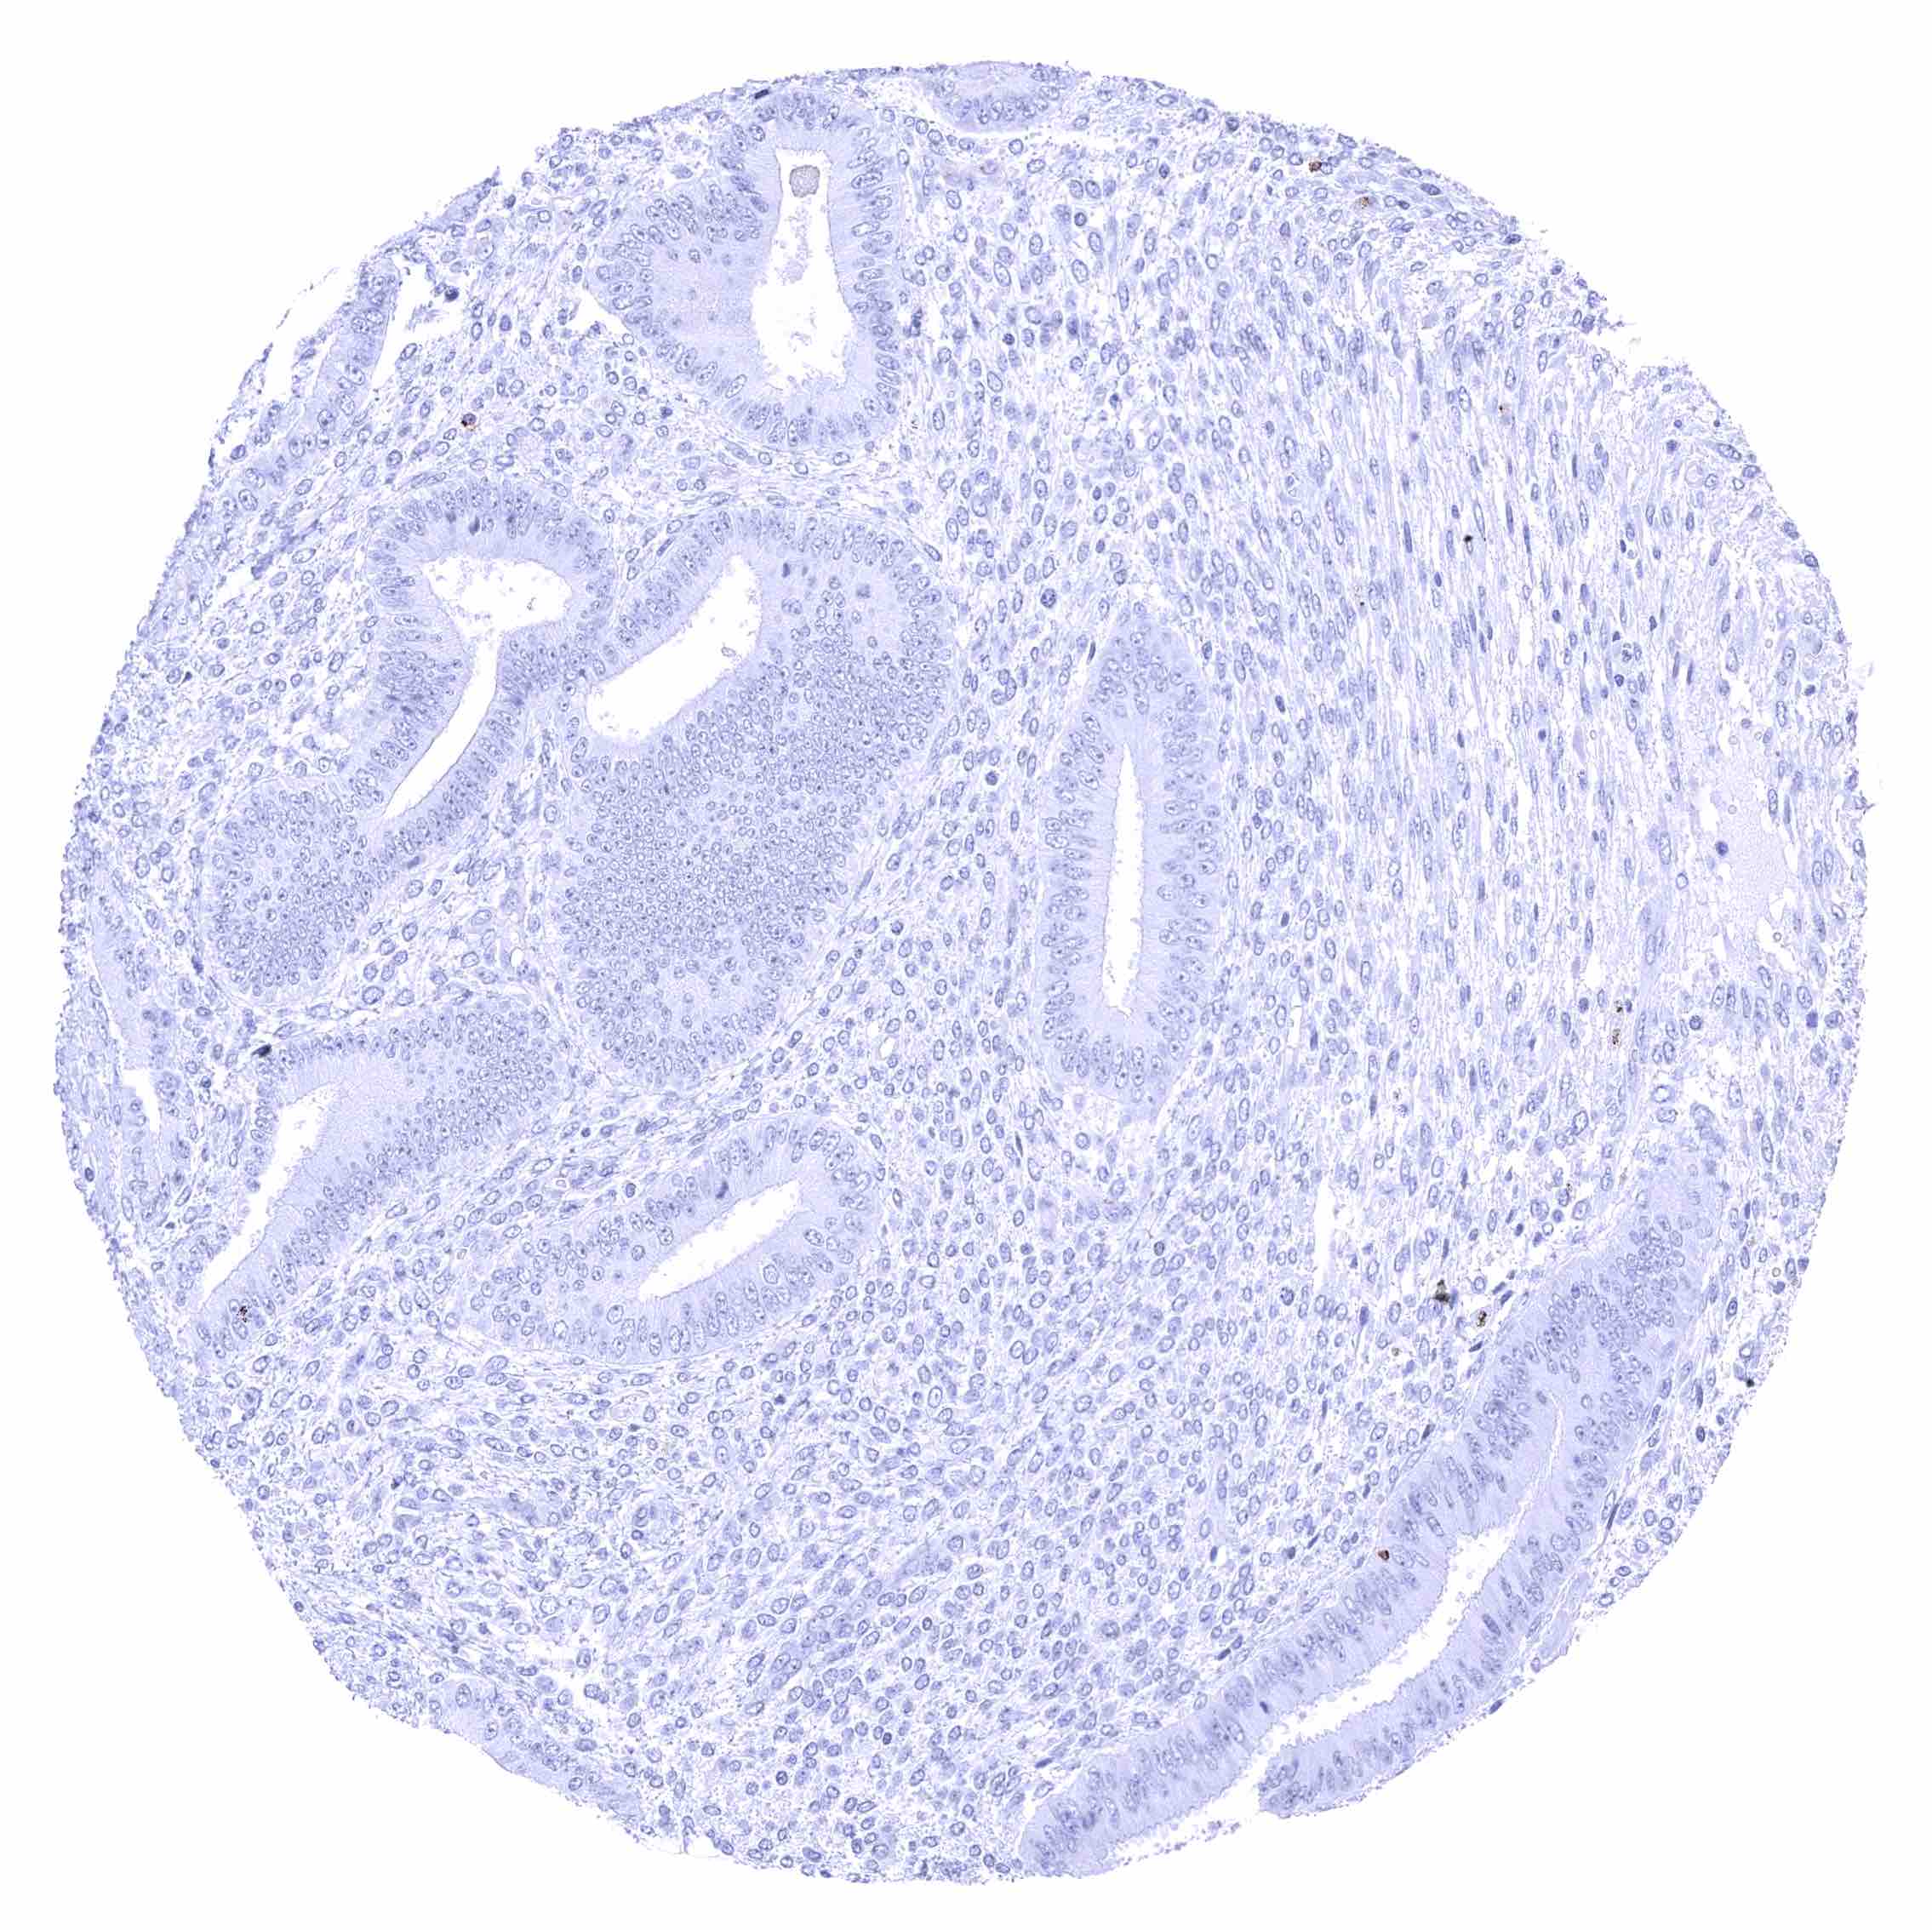

Prostate